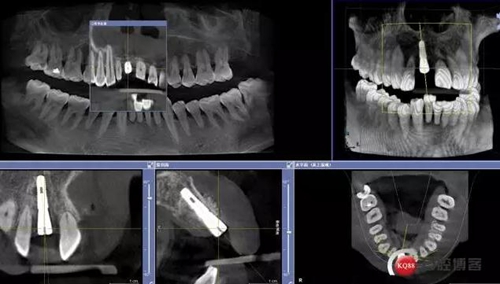

術(shù)后CBCT